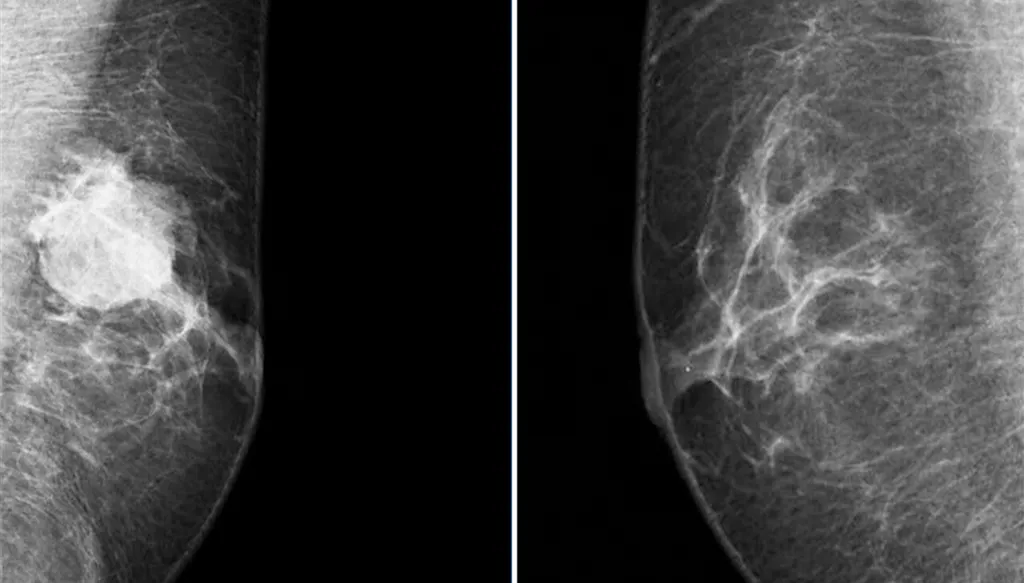

كيف يتم تشخيص المرض؟

غالباً ما يتم اللجوء أولاً إلى صورة صوتية بعد ملاحظة علامة ما، ومن بعدها صورة شعاعية، قبل اللجوء إلى الخزعة. ويمكن اللجوء أيضاً إلى الخزعة في الغدد اللمفاوية.